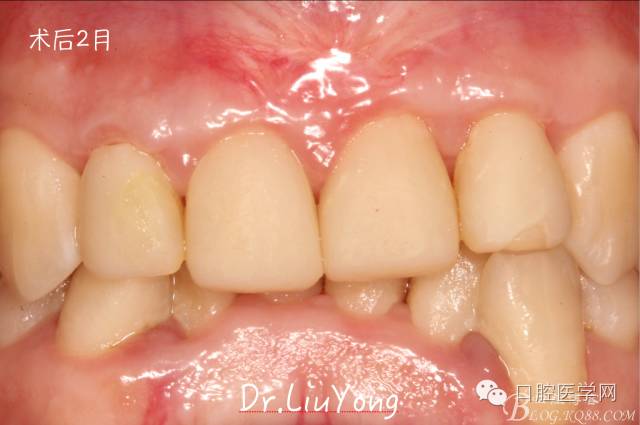

術(shù)后兩周,復(fù)查,A1達到了完全的根面覆蓋,B1牙齦退縮由原來的3.5mm減少到1mm,B2近中牙齦也得到部分的恢復(fù),同時所有牙齦邊緣都通過手術(shù)增厚。如上圖